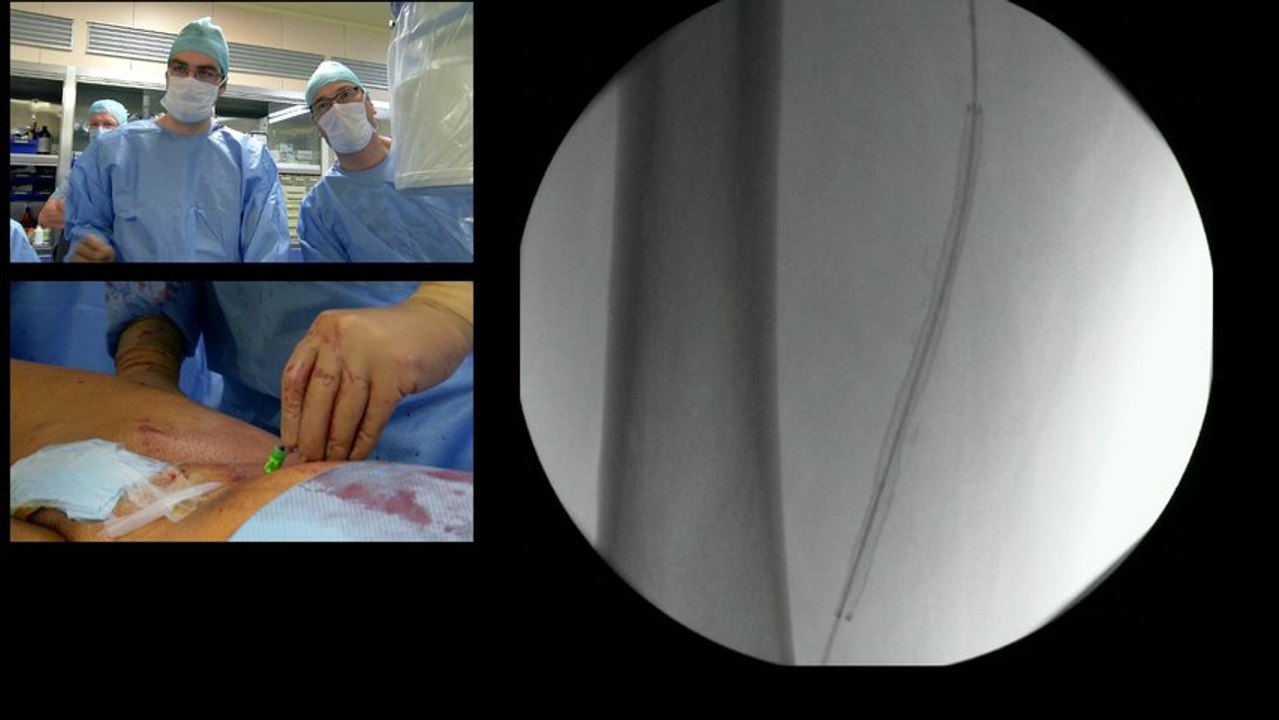

Endovascular Electronic Education : Discussions on recorded cases of CLI / BTK

Live from 35 th Charing Cross Symposium (London): ILEGx Collaboration Day